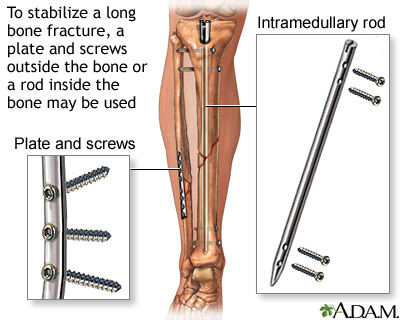

- If needed, immobilize the broken bone with a splint or sling. Possible splints include a rolled up newspaper or strips of wood. Immobilize the area both above and below the injured bone.